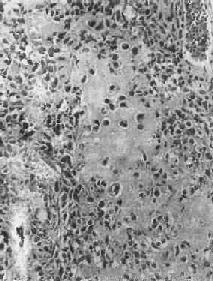

镜下,骨肉由明显间变的梭形或多边形肉细胞组成,细胞大小不等,核形奇异,大而深染,核仁明显,易见病理性核分裂像。肿细胞直接形成肿性类骨组织或骨组织,是诊断骨肉的最重要的组织学依据。所形成的类骨组织或骨组织在不同肿或同一肿的不同部位多少不等。往往可看到肿性骨质发生过程中各阶段的形态,最早期在恶性肿细胞间出现均质红染的胶原样物质,其后红染物质逐渐增多,将肿细胞分隔疏远,构成小梁或片状的肿性类骨组织(图17-8)。类骨组织可伴钙盐沉着,其内的肿细胞固缩变小,形成肿性骨质。骨肉内也可出现肿性软骨(图17-9)。

图17-8 骨肉

多形性肉细胞直接形成肿性骨样组织